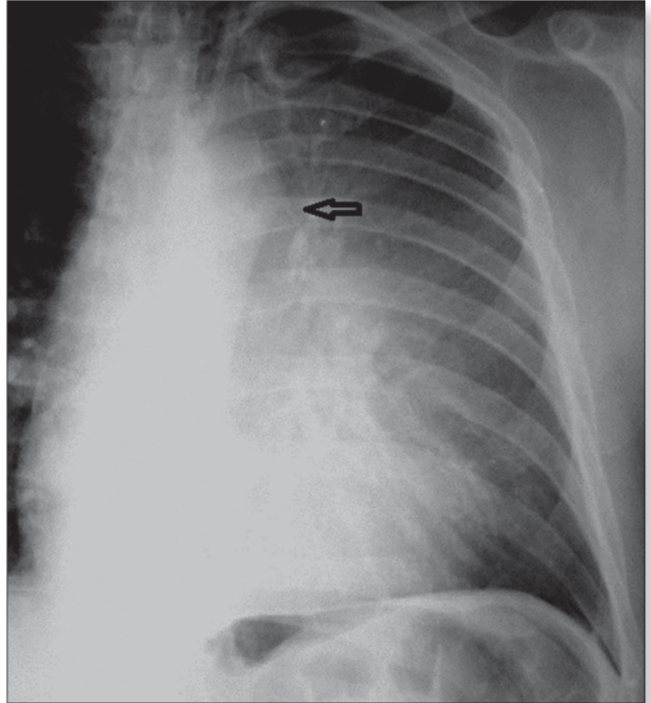

Signo de la cuña aérea o de Luftsichel

¿Cuándo se da el signo d?